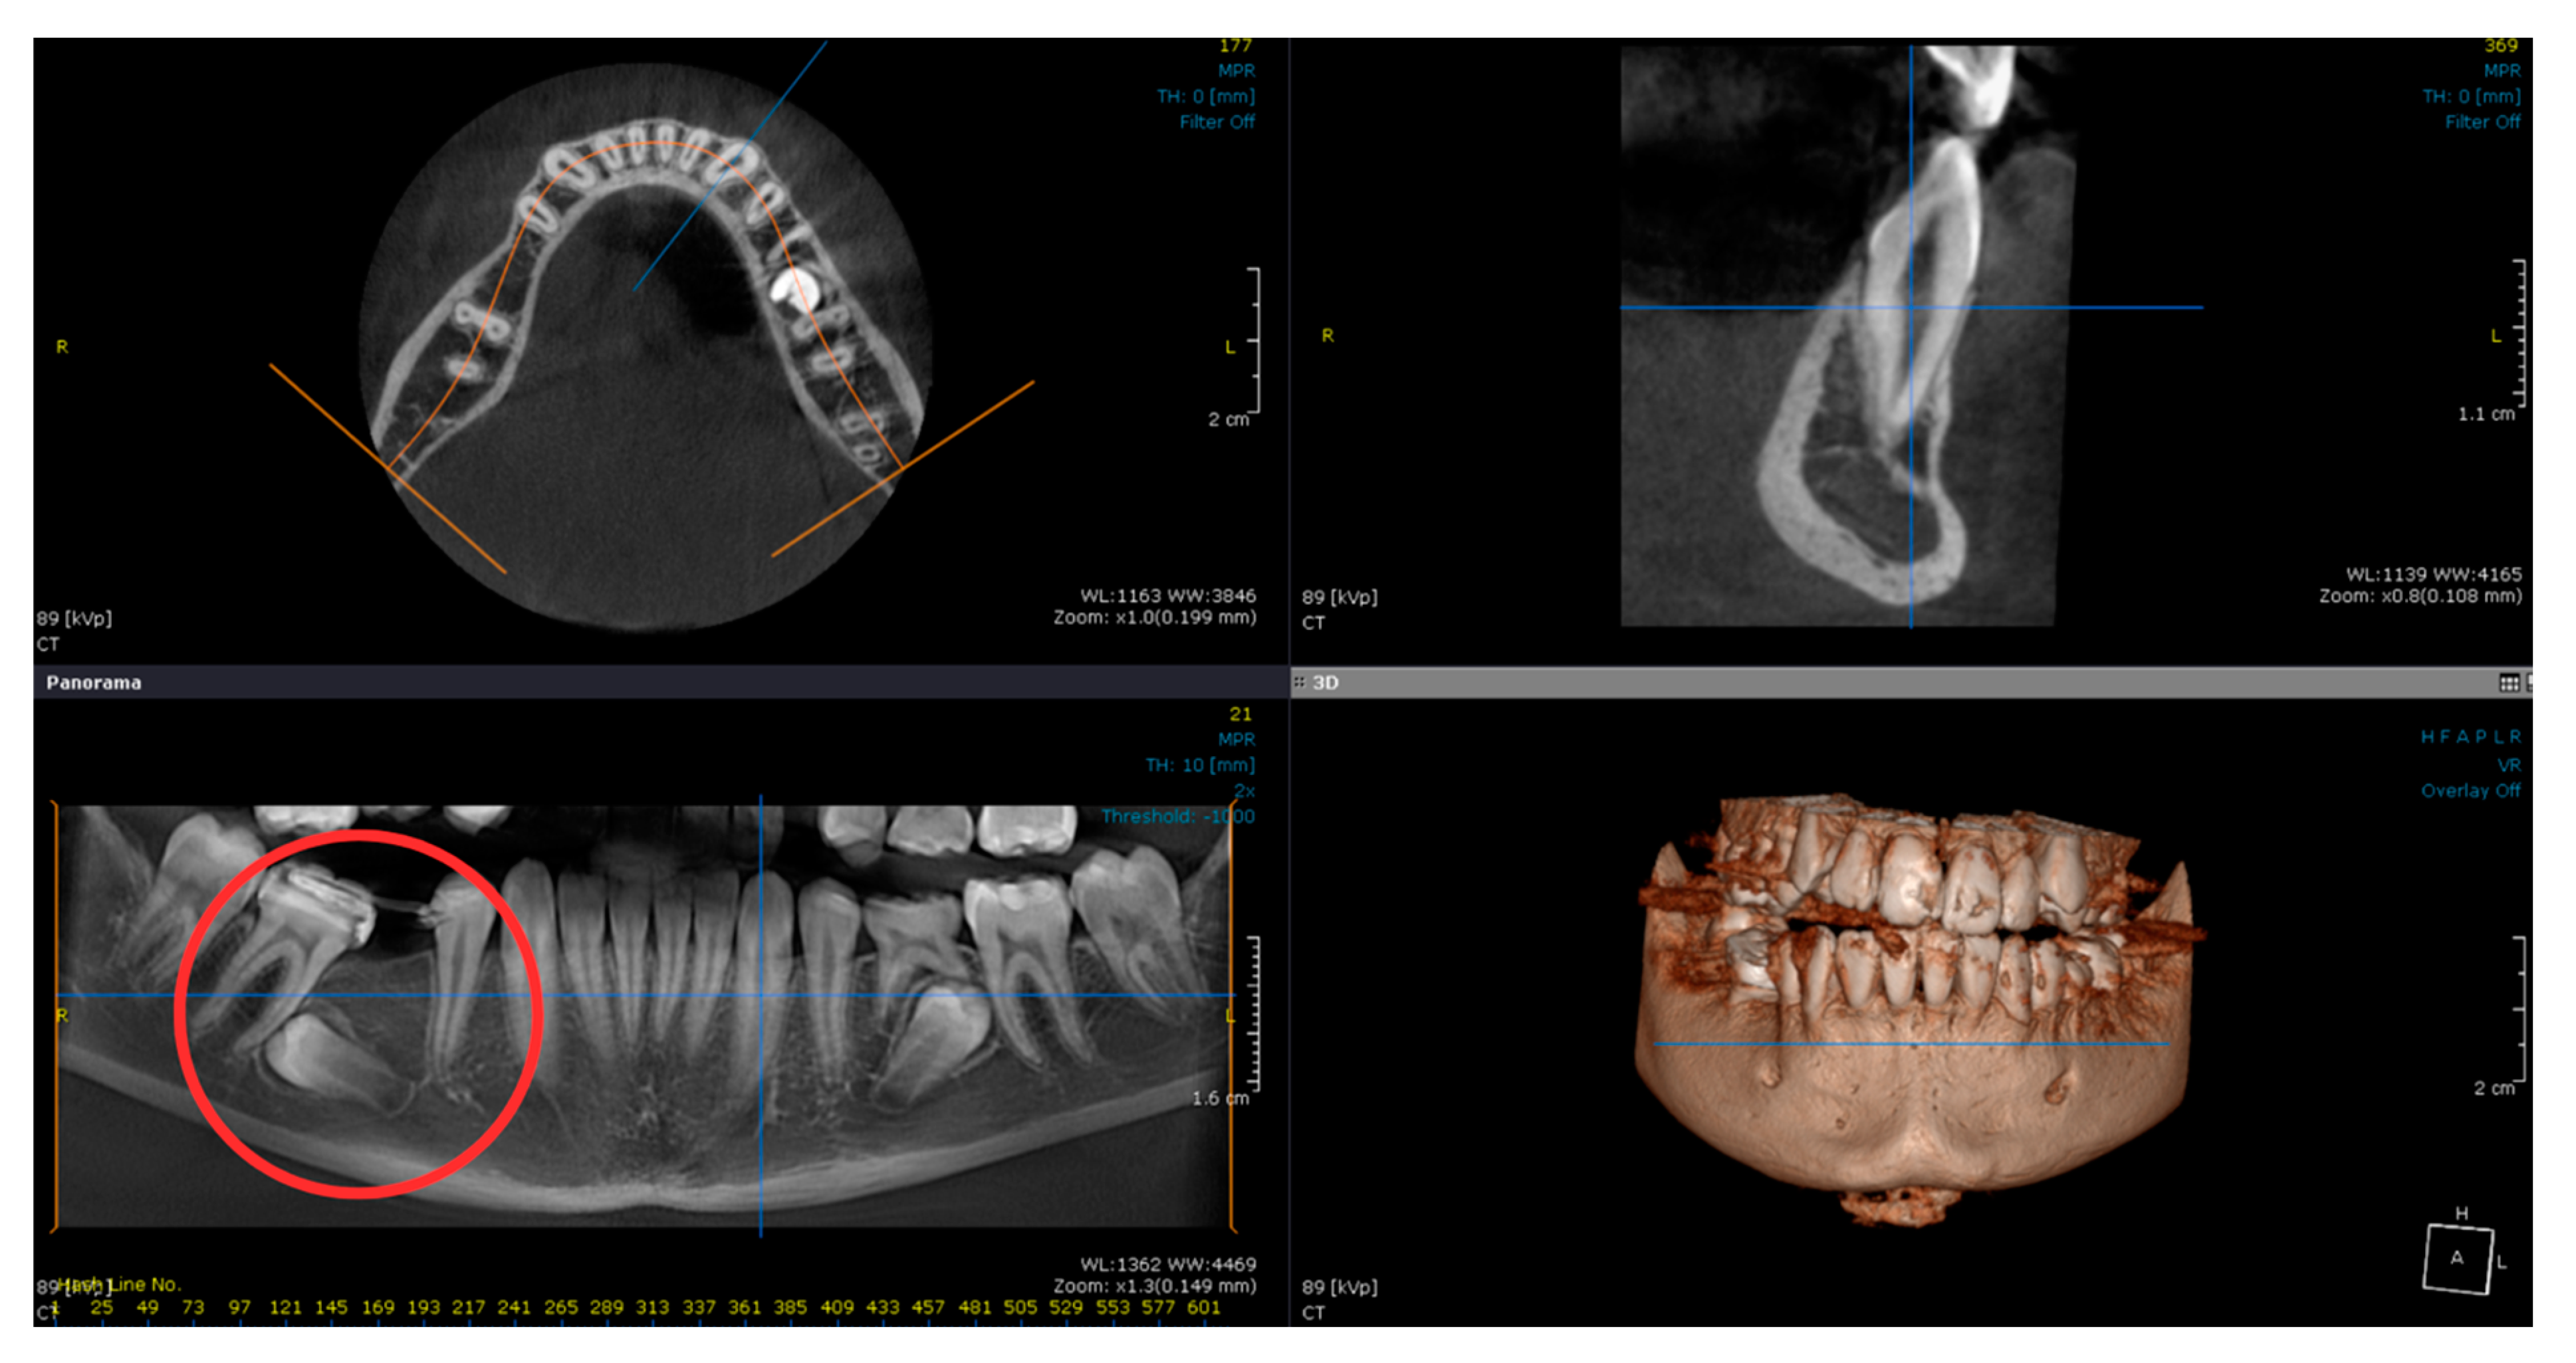

2. Case Report

2.1. Examination, Diagnostics, and Initial Therapeutic Management

2.2. Treatment Plan